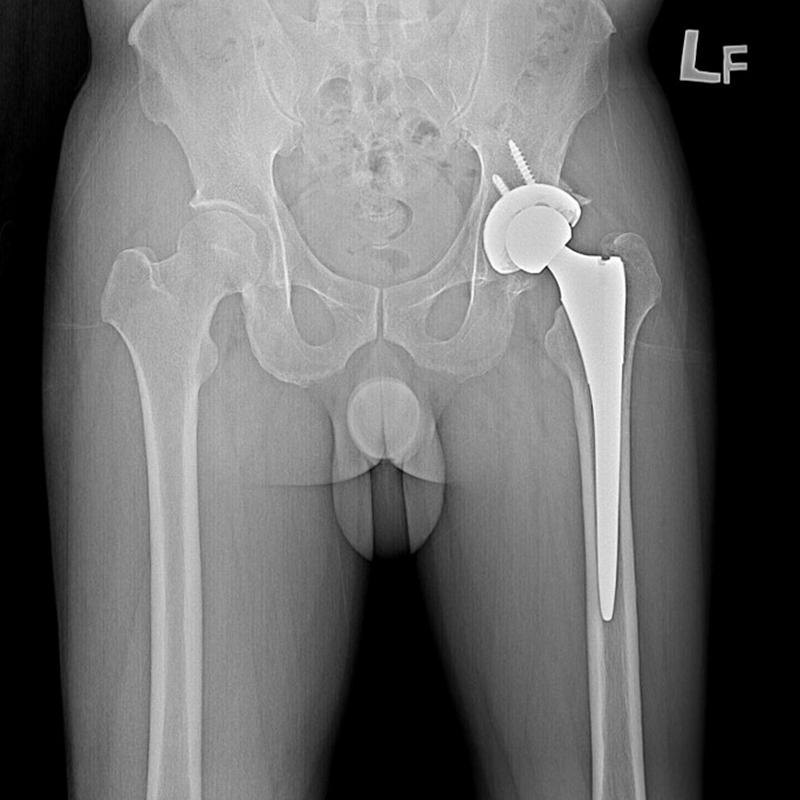

傳統髖關節置換 首頁 案例分享 髖關節手術 傳統髖關節置換 54歲蔡先生退化性關節炎 術前 術後 張女士 51歲 退化性關節炎(DDH先天發育不全 CROWE TYPE 2) 術前 術後 38歲林先生 退化性關節炎 術前 術後 72歲謝女士 退化性關節炎 術前 術後 71歲 謬女士 骨股頭壞死 術前 術後 50歲 郭先生骨股頭壞死 術前 術後 80歲 盧先生骨股頭壞死 術前 術後 林先生 37歲 術前 術後 邱女士 51歲 術前 術後 張女士 50歲 術前 術後